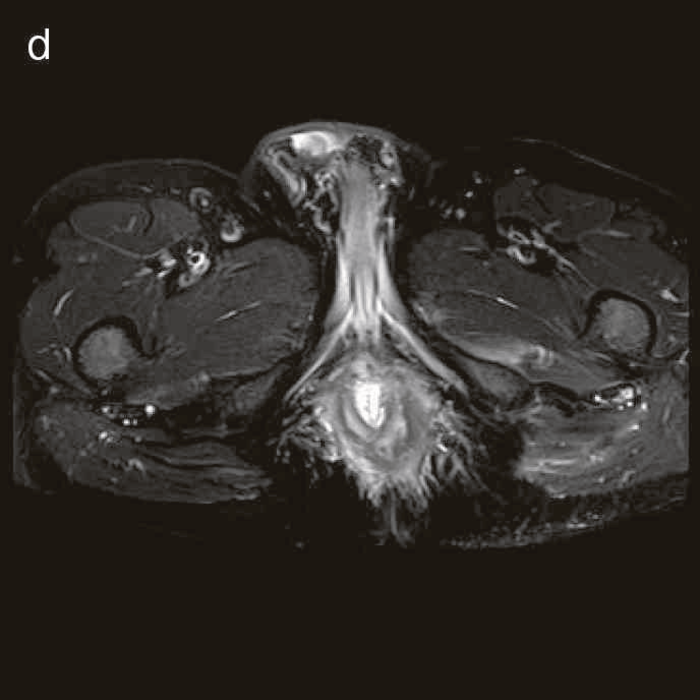

図38 骨盤部MRI

術前の骨盤部MRIでは右側の痔瘻瘻管と,左側の瘻管,周囲のリンパ節腫大を認めた。

明らかな癌を示す所見は不明であった。